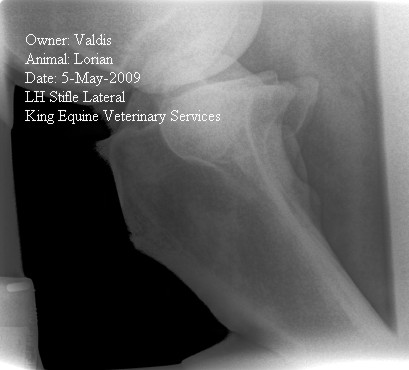

Posted on Thursday, May 14, 2009 - 12:51 pm: Dear Dr. O.,Thank you for your quick response. I have asked myself how could it get this bad this fast. As background information though, my horse has had warm up lameness off and on, just not enough to be locatable. He has had troubles with certain dressage movements which has given me "this feeling" that something is wrong for a long time and I thought about getting him x-rayed just for that, but again, nobody was sure which joint is causing it. I think now it finally manifested itself in a real noticeable lameness. Another indicator for pain is his change in behavior. He started turning unpredictably aggressive over the winter. He is on bute now and seems much happier again, but that’s not a long term option as he already had ulcers in the past. Surgery is not really an option because he can’t be stall rested as he jumps and paces in his stall the second the barn door opens. Only option seems Depo injections or IRAP, but if none of these will get him sound again one really has to question it. I attached some x-rays, but with this low resolution I don’t know how much you will see. The vets and surgeon looked at it on a high res screen. What do you think?

Posted on Monday, May 18, 2009 - 11:24 am: Delia, in the first image I do think the opacity that spans the front of the joint just cranial to the tibial tuberosity could represent a mineralized cranial border of the meniscus but I would want a radiologist to review this as it is not a lesion I have seen before and I cannot find an example of it in any of the references I have. It also has an irregular of "fibrillated" appearance. We also see several osteophytes (bone spurs) and the one on the proximal tibia has been associated with chronic meniscus injuries.Most of these cases do have a poor prognosis without surgery and even with surgery to debride torn tissue and possible suture any partially torn ligaments the prognosis is improved but still guarded. DrO |

Posted on Monday, May 18, 2009 - 8:52 pm: Thank you Dr.O,The radiologist and the surgeon at our university clinic reviewed these x-rays and were the ones who told my local vet that the lateral meniscus is entirely calcified. We all think that my horse must have had an injury in his early years. I have owned this horse for 3.5 years and he certainly didn't incur this injury during that time. He came to me in very poor condition from some backyard breeder who had neglected him, hence I didn’t get a PPE done and never had him x-rayed. By chronic meniscus injury you mean an injury that never healed up properly or an injury that keeps recurring? Looking at these x-rays – would you expect to see torn ligaments? Only way to find out is surgery, correct? Could he even have been sound for all this time with a torn ligament? That “fibrillated” mass in front of the joint – if it’s not some sort of calcification, what else could it be? If surgery is not really an option for previously described reasons what potential treatment would you chose and why? Thank you again for looking at this and sharing your insights |

Posted on Tuesday, May 19, 2009 - 9:37 am: Delia,You would not expect to see torn ligaments radiographically and yes surgery required for a better diagnosis. Because everyone's goals, resources, and willingness to assume risk are different, I cannot make useful specific recommendations for you. Our recommendations for treating arthritis, including IRAP, are put forward in the article on Overview of Arthritis and details of most of the treatments are fleshed out in detail in their own articles which are linked to from the arthritis article. Whatever your decision is must be based on the notion that the prognosis for return to soundness is poor based on the radiographic findings. I think your history suggests a slightly better prognosis however. Though I have not seen such an appearance I think that fibrillated mass in the cranial extent of the calcified meniscus. DrO |